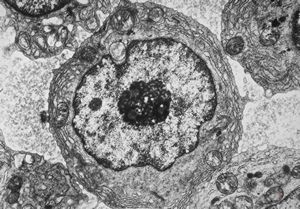

F,72y. | blood - lymphoplasmocellular leukemia

F,61y. | blood - lymphoplasmocellular leukemia